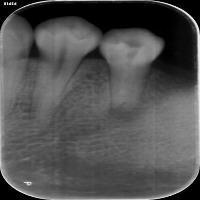

Dental Health Monitoring: This computer vision model can be used by dental professionals and healthcare providers to monitor patients' dental health by evaluating teeth x-rays and identifying specific classes to detect decay, infections, or tooth misalignment.

Dental Education and Training: Dental students and professionals can leverage this model as a learning tool to study and understand different vqc classes, such as P3, P4, and P5, and their implications in various dental conditions and their corresponding required treatments.

Customized Orthodontic Treatment Planning: The model can analyze x-rays to identify individual tooth structure, allowing orthodontists to create customized and more precise treatment plans for improving dental alignment and addressing various occlusion issues.